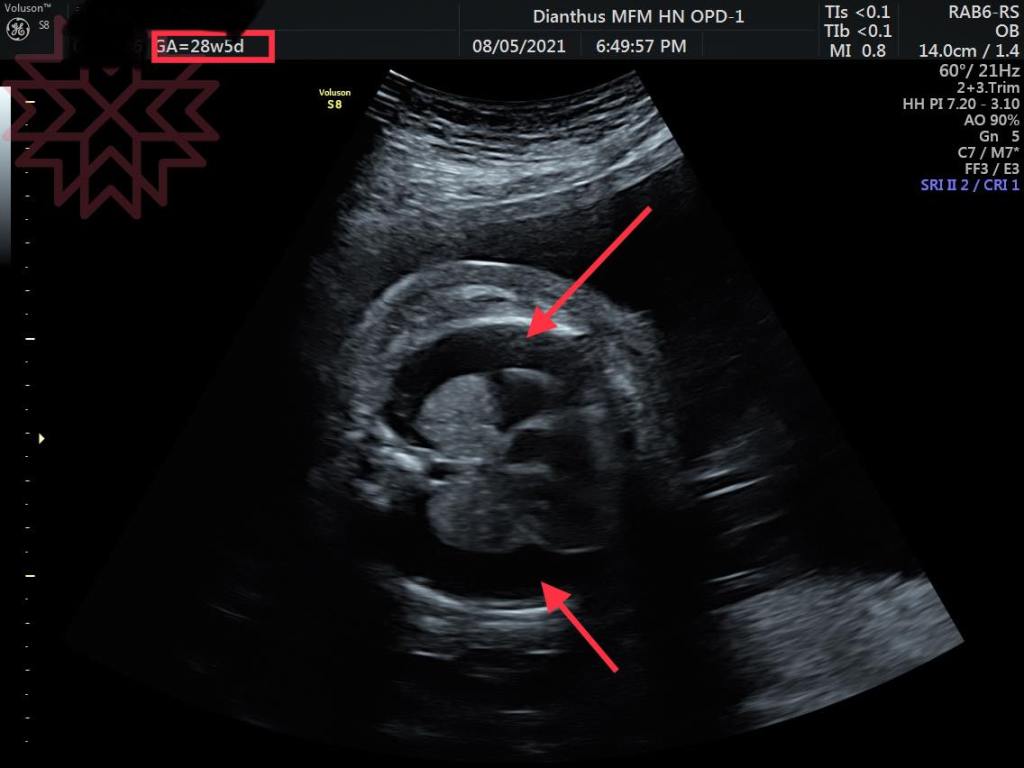

第二張是28周治療一個星期之後的照片

還是胎兒雙側乳糜胸